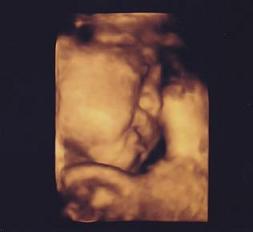

初めて、赤ちゃんの4Dエコー写真をいただきました!

今注目の(?)4Dエコーというのが見れるそうなんです。

初めて、4Dの超音波写真というものをいただきましたー!!

コチラです!!↓

すごいー!!Σ(゚д゚;)

カラーであるのと、

その鮮明さ

にビックリ!!お見せできないのが残念ですが、

細かい動きもしっかり見れて、

お口部分をパクパクしていている姿が

とっっても可愛かったです(*´∇`*)♪

あ、ちなみに、

もう妊娠32週なので全身は写りません。

写真は横顔と片腕です。(分かるかな??)